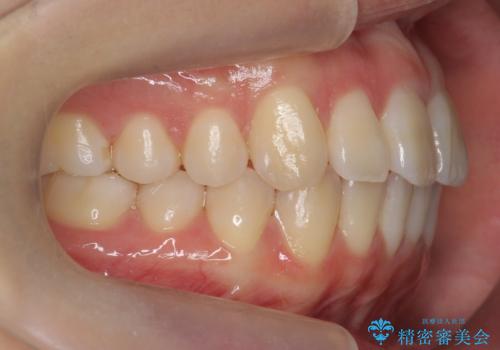

インビザライン モニター治療 前歯のねじれをまっすぐに

- 前歯のねじれを主訴に来院。

インビザラインの部分矯正コースではなく全体矯正コースをご希望でした。

前歯のねじれやがたつきだったため、モニター治療での低価格でのご提案が可能でした。

年齢が10代なこともあり、歯の動きは非常によく、リファインメントなしできれいに並びました。

下の前歯を少し削合して並べています。